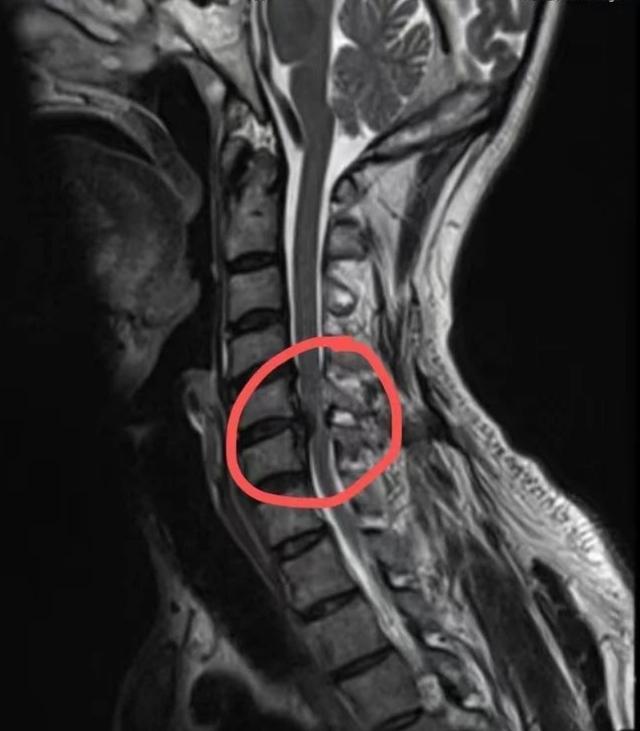

(▲脊髓型颈椎病核磁共振表现

颈部脊髓受压变形、变性)